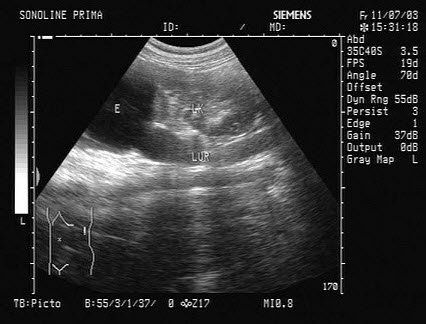

85、单项选择题

女,25岁,因急性胰腺炎禁食5天。声像图如图所示。结合超声声像图,诊断为()